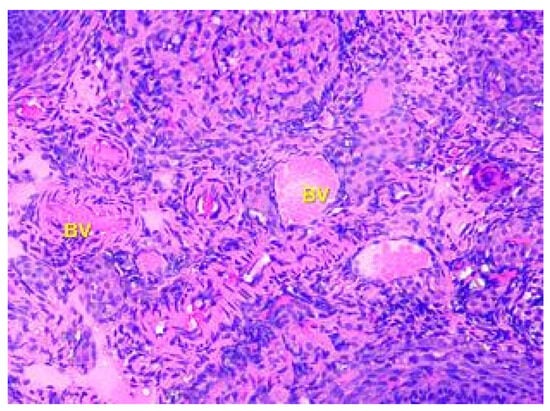

- Denefil, O.V.; Bilyk, Y.O.; Chorniy, S.V.; Fedoniuk, L.Y.; Chornii, N.V. The peculiarities of morpological changes of rats’ ovary and biochemical state under the damage with different doses of lead acetate. Wiad Lek. 2022, 75, 377–382. [Google Scholar] [CrossRef] [PubMed]